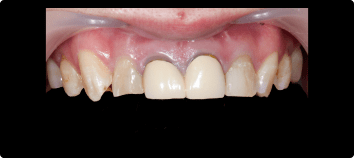

前歯を綺麗に治したい

BEFORE

AFTER

症例概要

年代・性別

50歳代 女性

主訴

治療内容

上顎両側1番インプラント、上顎両側2番セラミッククラウン、根管治療

治療期間

4ヶ月

治療のリスク

骨が少ない場合や膿の大きさが大きい場合は同時にできない場合があります。

治療費用

1,210,000円(税込)